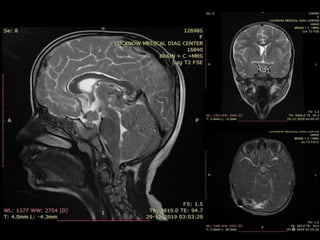

MR FINDINGS

• Iso- to slightly hyperintense to cortex on T1- and T2WI.

• T2* (GRE, SWI) may show “blooming” due to intratumoral

calcification.

• Enhancement is strong and usually homogeneous .

• Because of their high cellularity, germinomas may show

restricted diffusion.

CASE SUMMARY

• 9yr old female patient present with headache and

numbness of limbs

• On imaging shows Relatively well define

hetrogenous enhancing mass lesion in pineal region

and concurrent suprasellar mass with

leptomeningeal spread

• Likely Diagnosis is GERMINOMA

• HPE is awaited

MR FINDINGS • Iso-to slightly hyperintense to cortex on T1- and T2WI. • T2* (GRE, SWI) may show “blooming” due to intratumoral calcification. • Enhancement is strong and usually homogeneous . • Because of their high cellularity, germinomas may show restricted diffusion. 16

CASE SUMMARY • 9yrold female patient present with headache and numbness of limbs • On imaging shows Relatively well define hetrogenous enhancing mass lesion in pineal region and concurrent suprasellar mass with leptomeningeal spread • Likely Diagnosis is GERMINOMA • HPE is awaited 22

• #17 Sagittal MRI T2WI (a) , T1WI (b) and T1WI+C (c) showing a T1 and T2 isointense germinoma with homogenous post contrast enhancement